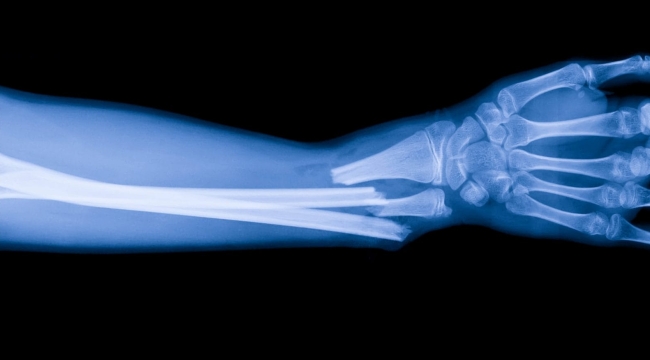

Cho Sun Daily'nin haberine göre bir deneme vakasında, bilek kırığı olan bir hastaya sadece 3 cm’lik bir kesiden bir enjeksiyon yapıldı ve yalnızca üç dakikada iyileşti. Bu yapıştırıcı olmasaydı, bileği onarmak için metal plaka ve vidaların gerekeceği bir ameliyat yapılacak ve ayrıca bir yıl sonra bunları çıkarmak için ikinci bir ameliyat daha olacaktı. Üç aylık takip muayenesinde hastanın kırığının komplikasyonsuz olarak tamamen iyileştiği bildirildi.

“Bone-02” ayrıca, kemik iyileştikçe vücut tarafından doğal olarak emilebiliyor, böylece implantları çıkarmak için ikinci bir ameliyat gerekliliğini ortadan kaldırıyor. İlk testler ayrıca, kemik yapıştırıcısı kullanıldığında metal plaka prosedürlerine kıyasla daha az enfeksiyon görüldüğünü de ortaya koyuyor.